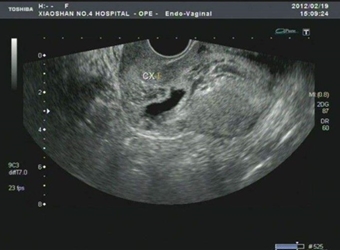

胎儿入盆,是孕晚期一项重要的分娩前准备!很多孕妈都在疑问一个问题,已经入盆b超单如何显示?想知道胎儿是否已经入盆,b超单上究竟是如何显示的呢?有没有相…